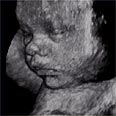

חדש: אולטרסאונד תלת מימדי לנשים הרות

התמונה הברורה מתקבלת לאחר שהמכשיר מצלם 300 תמונות של העובר בחלקיקי שניות ומחבר אותן. על צג המחשב מופיעה תמונה תלת מימדית של העובר, ברורה בהרבה מהתמונה המוכרת שמספק אולטרסאונד דו מימדי רגיל.

תמונת תלת המימד. "הנשכרת העיקרית היא האם"